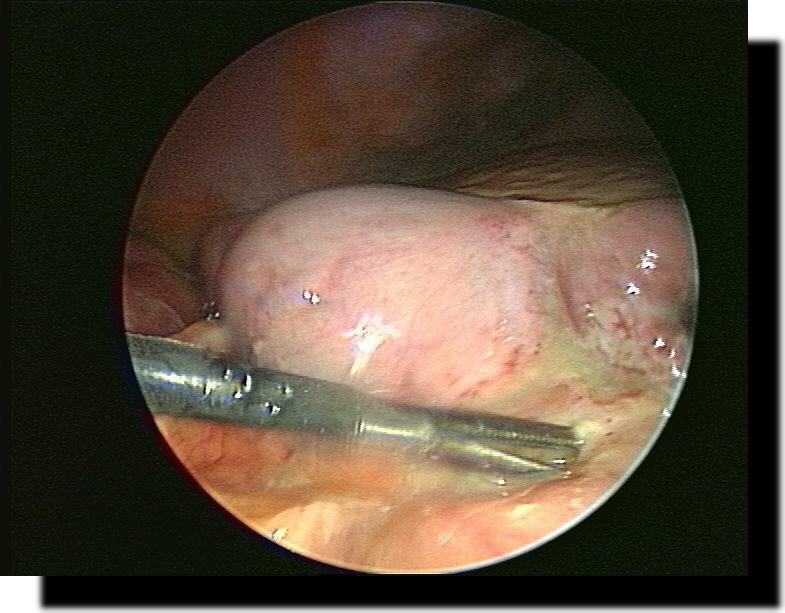

Restappendix nach konventioneller Appendektomie